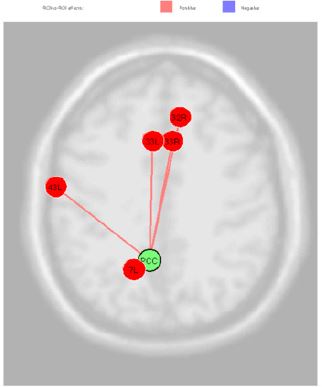

From the data activation exhibited in the previous picture we can calculate the connectivity metric applying the SVD, singular value decomposition, method to the time serial covariance matrix of BOLD signals from the voxel and clusters of voxels. These data report a voxel mapping as report in the following picture. It is important highlight that correlation between these areas can be positive and negative. Data of connectivity calculated on the activation measures of the previous figure are exhibited in the Figure 2. Starting by the BA(43), the area involved in the taste processing, we can consider the connection towards several areas connected to the DMN, as the PCC (posterior cingulate cortex); this is the upper part of the “limbic lobe”. The cingulate cortex is made up of an area around the midline of the brain. Surrounding areas include the retrosplenial cortex and the precuneus. Efforts to understand the functional architecture of the brain have consistently identified multiple overlapping large-scale neural networks that are observable across multiple states. Despite the ubiquity of these networks, it remains unclear how regions within these large-scale neural networks interact to orchestrate behavior.

Figure 2: Voxel to Voxel mapping for correlations with positive and negative connectivity colors of areas (Blu =positive; red=negative).

Given that the precuneus is a Functional Core of the Default- Mode Network our subjects are requested to do no tasks during fcMRI sessions, [14]. During the first part of the experiment they simply stay in idle, by standing still and trying to leave the mind wandering without a specific topic. In the second session of fcMRI they were requested to experiment the bitter taste of the propylthiouracil. In these conditions the BA (43) exhibit correlation with Anterior Cingulate Cortex (right and left BA33, the Subcentral Area, the Somatosensory Associative Cortex and Dorsal Anterior Cingulate Cortex Figure 3. The PCC source was directly correlated Anterior Cingulate Cortex (right) (beta 0.16; p=0.02), Anterior Cingulate Cortex (left) (beta 0.17; p=0.02), Subcentral Area “Gustatory Cortical Area” (right) (beta 0.16; p=0.03), Somatosensory Associative Cortex (left) (beta 0.13; p=0.03) and Dorsal Anterior Cingulate Cortex (right) (beta 0.10; p=0.04) Figure 4.